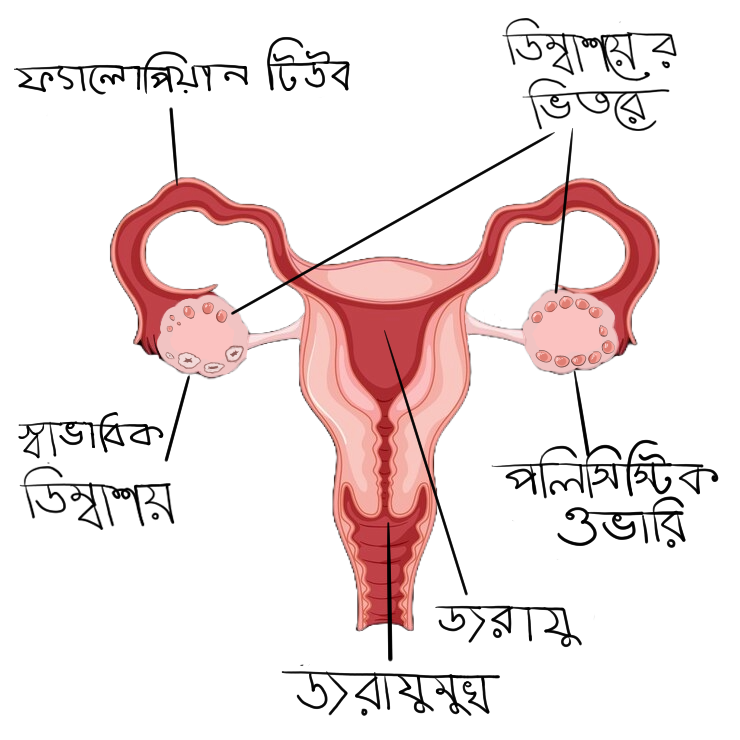

পলিসিস্টিক ওভারি সিনড্রোম হল ডিম্বাশয়ে অ্যান্ড্রোজেন নামক অতিরিক্ত হরমোন তৈরির ফলে হরমোনের ভারসাম্যহীনতার ফলাফল। এই অবস্থা বন্ধ্যাত্বের কারণ হতে পারে এবং অন্যান্য স্বাস্থ্যগত অবস্থার ঝুঁকি বাড়াতে পারে।

- পলিসিস্টিক ওভারি।

It is a result of hormonal imbalance from the creation of excess hormones in the ovaries called androgens. This condition can cause infertility and increase risk to other health conditions.

- Polycystic ovaries.